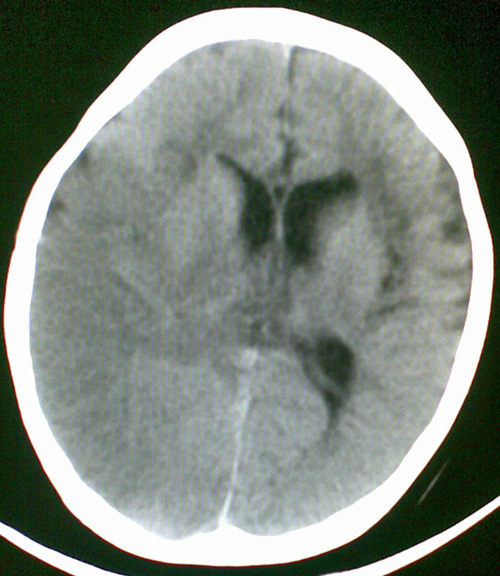

男4岁,反复抽搐多年,今早再次大抽搐,伴昏迷

考虑---右侧大脑半球脑梗死

右侧大脑半球密度减低,脑组织肿胀,占位?建议增强。

考虑脑梗塞. kaolv 血管病变---烟雾病可能

1)右侧大脑半球大面积脑梗塞。2)双侧额叶脑软化灶。3)脑萎缩。

建议:必要时行dsa检查排除烟雾病可能。

右侧半球梗塞,多发软化灶,考虑血管畸形继发,进一步检查。

右侧大脑半球大面积脑梗塞。双侧额叶脑软化灶。考虑血管畸形继发,建议进一步检查。

1右侧大面积脑梗死2左侧额颞部软化灶。